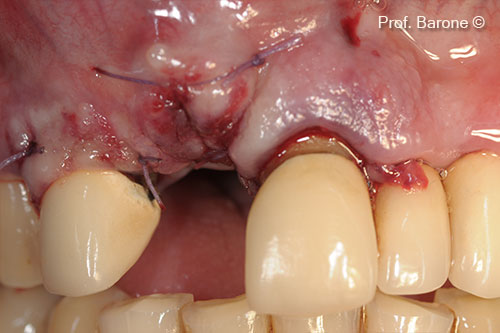

Lamina soft giúp bảo vệ mô mềm

Khâu kín mô mềm

Quá trình lành vết thương mô mềm sau 6 tháng